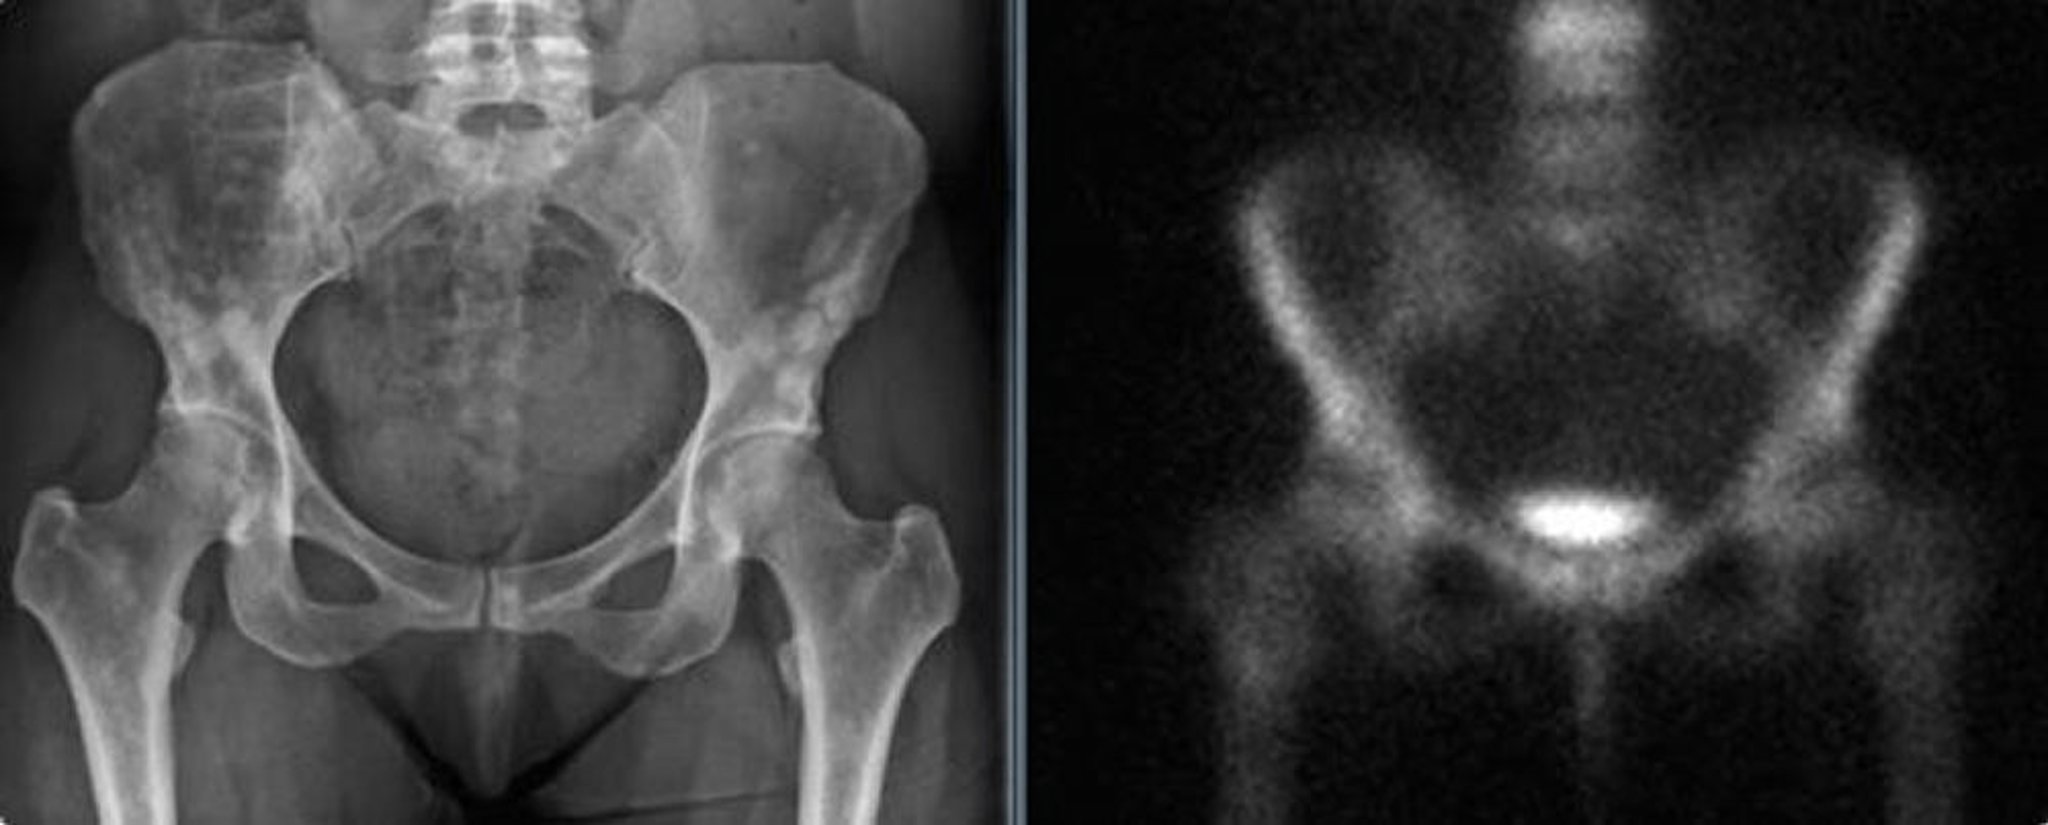

Bệnh xương đặc đốm ở xương chậu

Phim chụp X-quang vùng chậu (bên trái) cho thấy bệnh xương đặc đốm ở vùng chậu của một phụ nữ trưởng thành. Những chỗ tăng đậm độ này có thể bị nhầm lẫn với di căn nguyên bào. Phim chụp xương (bên phải) cho thấy không có gia tăng hấp thụ bức xạ đáng kể.

Hình ảnh do bác sĩ Michael J. Joyce và bác sĩ David M. Joyce cung cấp.